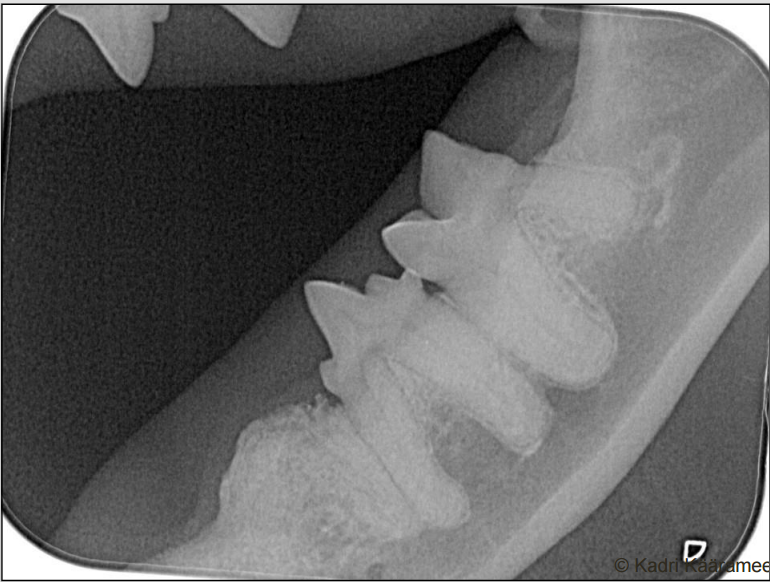

tooth resorption at the stage of healing where the crown has already fallen off and the gingiva has healed over leaving a faint bump where P3 used to be